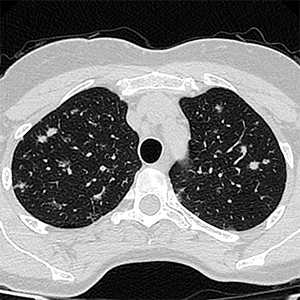

Noviembre 2025. Hospital Italiano

Masculino de 61 años. Masa dolorosa en cara anterior de pie derecho.